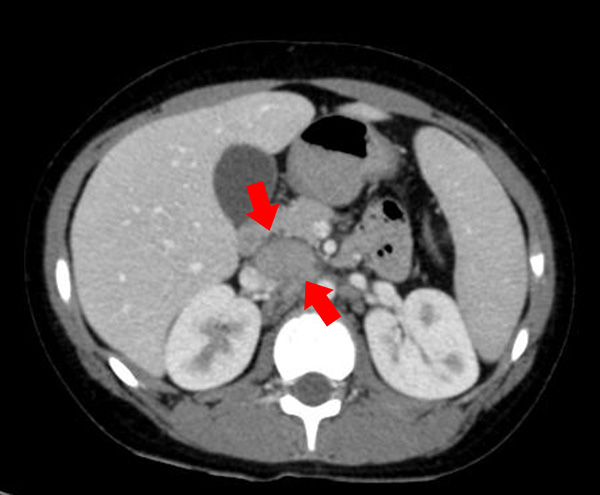

Valorizzando il dato anamnestico dei dolori addominali con febbre, seppur alla luce di una ecografia addome negativa, nel sospetto di una possibile raccolta ascessuale profonda abbiamo eseguito la TAC dell'addome con evidenza di una formazione ovoidale localizzata tra la vena cava superiore e la terza porzione duodenale a margine netti, con aspetto non colliquato, e la presenza di altre piccole formazioni ovoidali, reattive di diametro di circa 2 cm di diametro (Figura 1 e Figura 2).

Figura 1 e Figura 2. Formazione ovoidale solida a maggior diametro cranio-caudale di circa 4x3x2 cm tra vena cava superiore e terza porzione duodenale a margini netti, di aspetto non colliquato con presenza di altre formazioni ovoidali pi� piccole, reattive il maggiore di 2 cm di diametro.